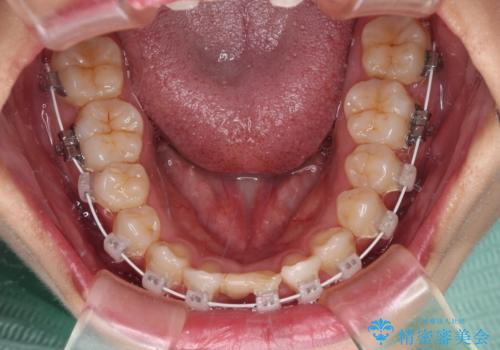

- 矯正装置

- 審美装置

ワイヤー装置により矯正治療を行うとともに舌突出癖改善のためのトレーニングをしっかりと行っていただき、咬み合わせが安定した位置となったタイミングで下顎前歯にブリッジの仮歯を装着していく計画としました。